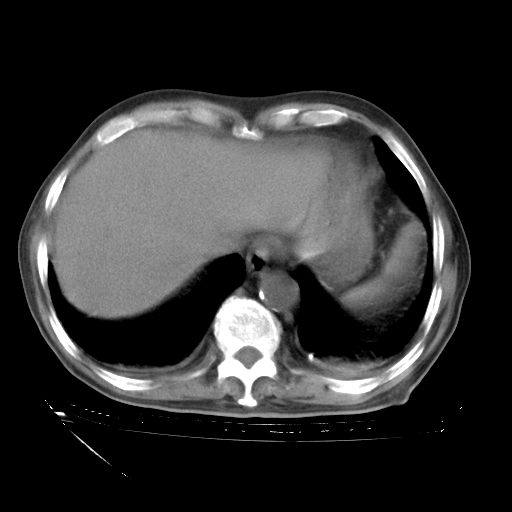

经过24天治疗,岳父的病情基本稳定。生活基本可以自理,可以下床活动。呼吸困难早已消失。体温基本正常。

只是甲强龙用80mg时血小板升到正常,改为60mg后又降到63×10*9/L。

主要治疗甲强龙80mg×14天,60mg×10天;同时抗结核(异烟肼+利福平+乙胺丁醇)。环磷酰胺0.1 tid 10天。

特别感谢胡教授、高管、桃子版主给出关键的治疗建议。桃版把所有肺部影像和全部临床资料请所在医院呼吸科、感染病科、结核科、临床免疫科专家会诊。临床免疫科专家制定了完整的治疗方案。